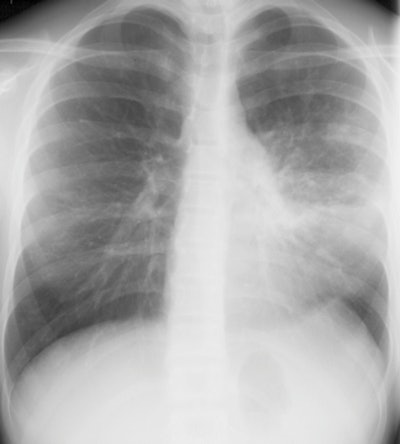

| A 13-year-old girl with pneumonia caused by Mycoplasma pneumoniae. Chest x-ray (above) and a contrast-enhanced 1.5-tesla coronal image (below). The MR image shows patchy parenchymal changes in both lungs. Images courtesy of the Department of Radiology, Turku University Hospital. |